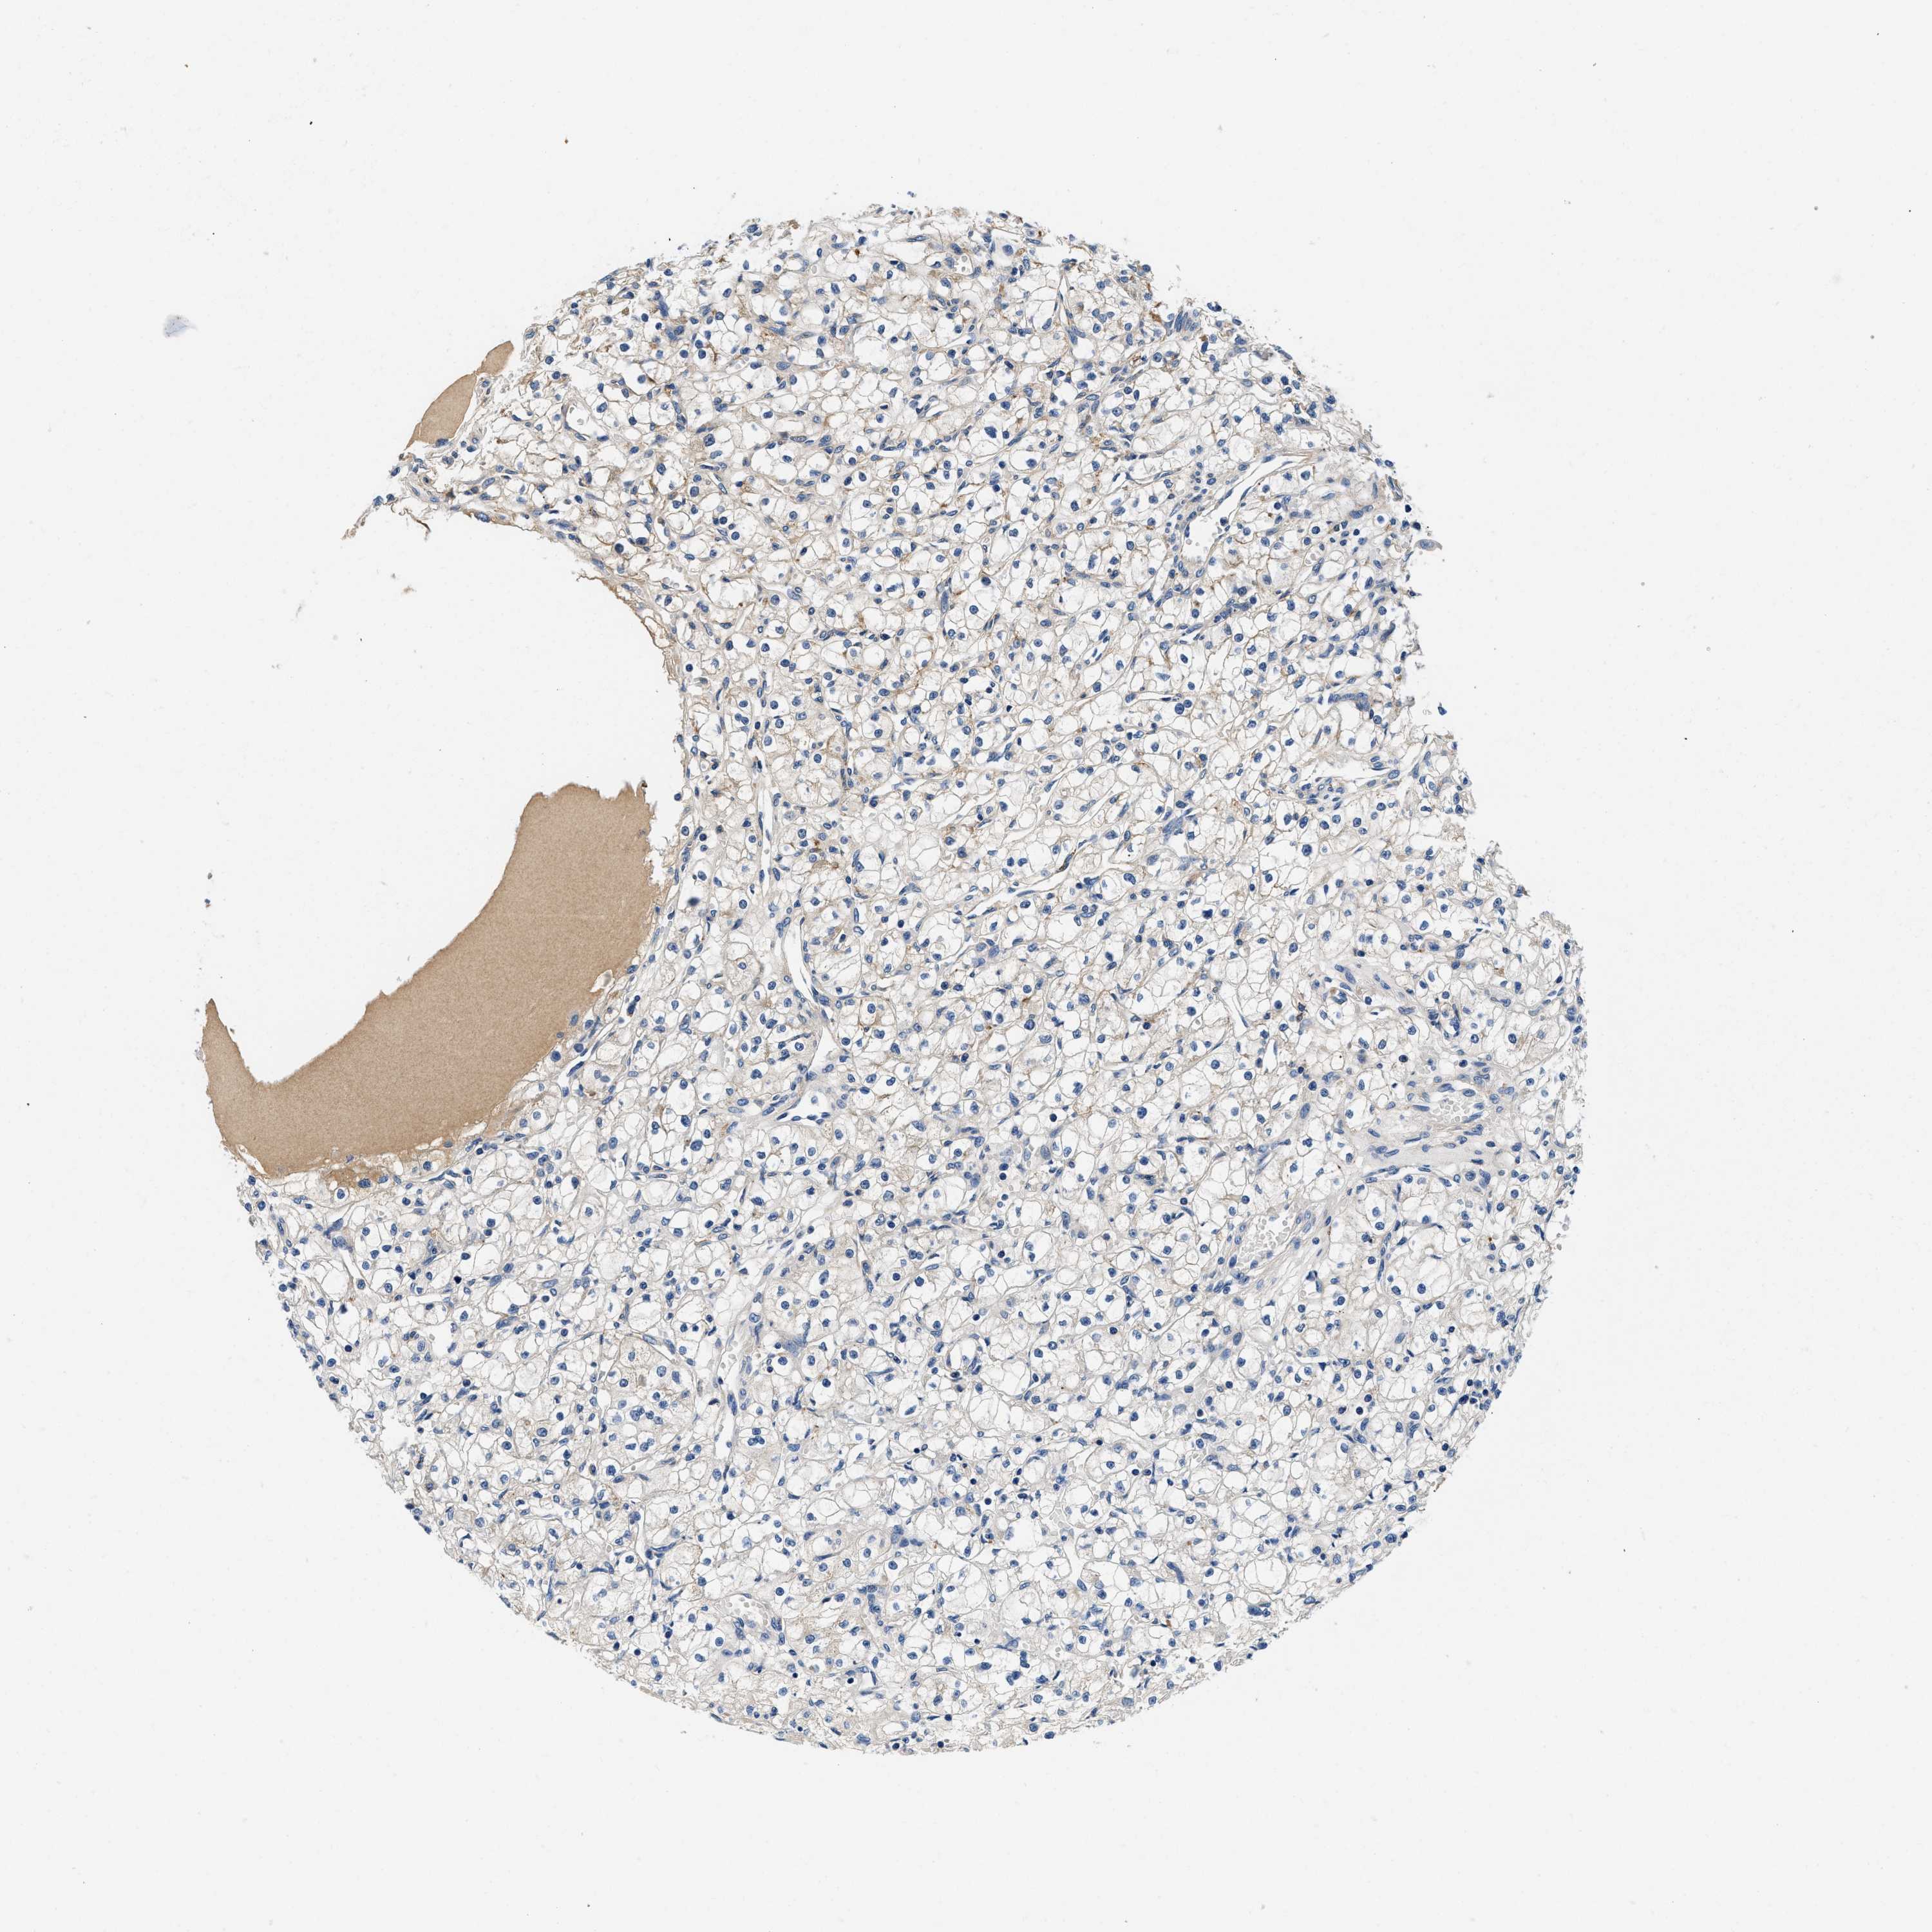

KIDNEY RENAL CLEAR CELL CARCINOMA (VALIDATION) - Interactive survival scatter ploti

ZFAND3 is not prognostic in Kidney Renal Clear Cell Carcinoma (validation)

: 52.03

Average pTPM 62.4

Number of samples 100